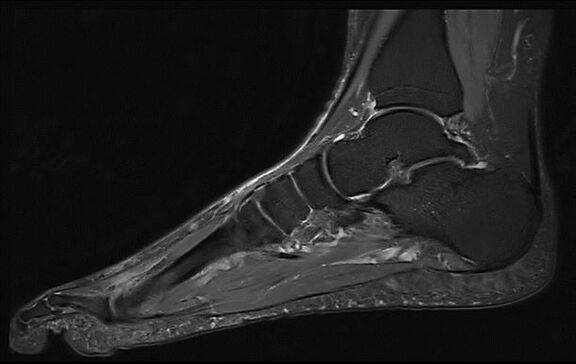

Beispiele von MRT-Fuß Aufnahmen

MRT-Bilder vom Fuß deuten

Die bei der Fuß-MRT aufgenommenen Bilder werden von unseren erfahrenen Radiologen ausgewertet und in einem schriftlichen Befundbericht dokumentiert. Dabei können zum Beispiel weiße Flecken auf den MRT-Bildern des Fußes auf verschiedene Strukturen oder Auffälligkeiten hinweisen. Die genaue Interpretation der MRT-Aufnahmen des Fußes obliegt dem zuständigen Facharzt, der die Ergebnisse im Zusammenhang mit Ihren individuellen Symptomen und Ihrer Vorgeschichte betrachtet und so die Diagnose stellt.